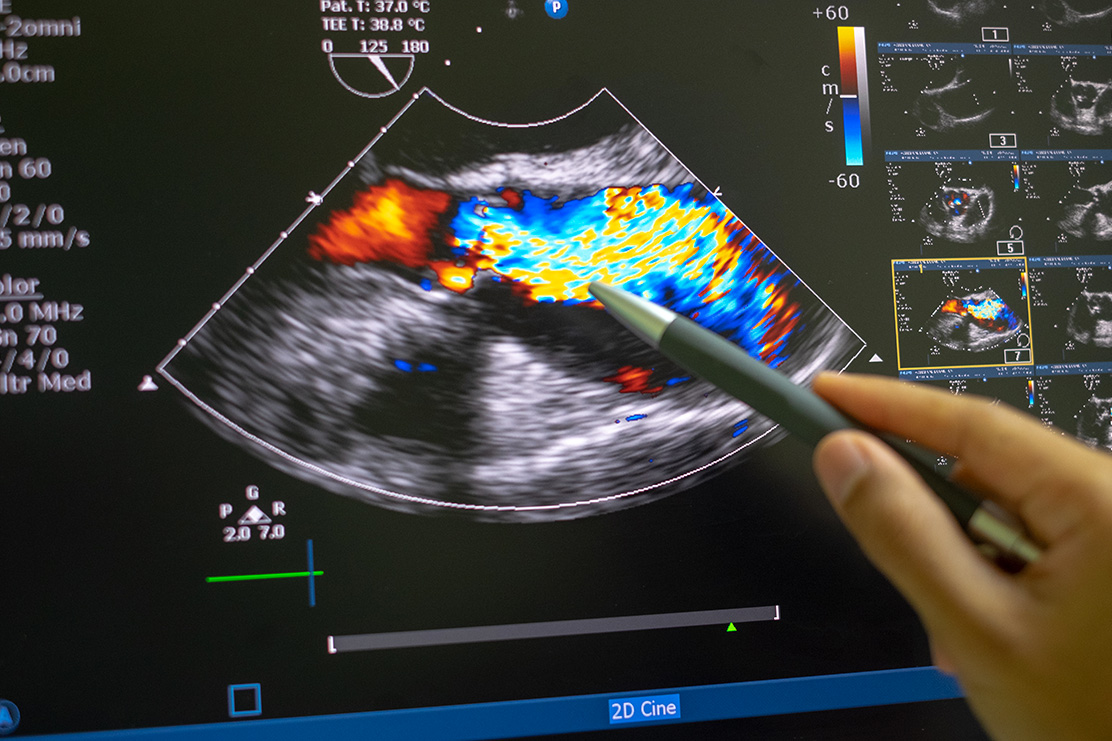

L’échographie-döppler est un examen simple et non douloureux qui permet d’évaluer la sévérité d’une sténose des troncs supra-aortiques. Cet examen va permettre de mesurer le pourcentage du rétrécissement de l’artère soit directement soit le plus souvent par le biais de l’accélération locale du flux sanguin, dans certain cas l’échographie peut enregistrer des embolies de petites taille (HEAT).